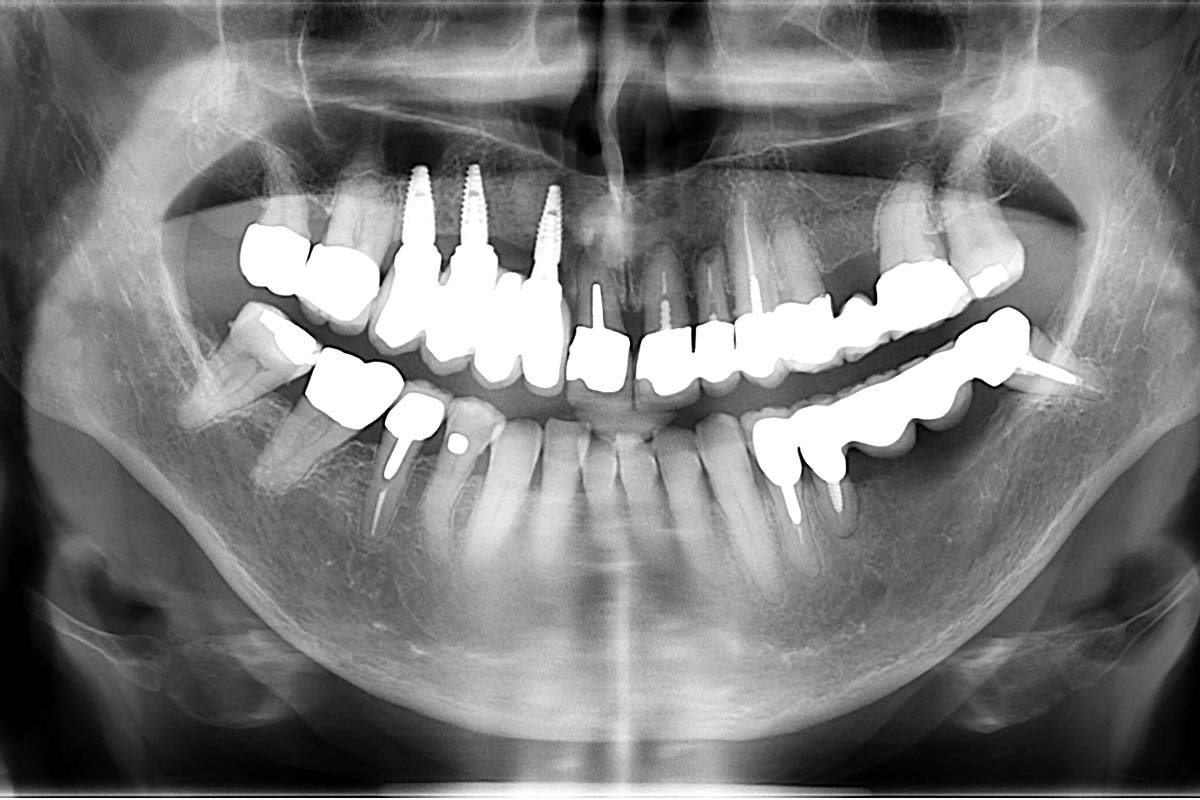

Full maxillary reconstruction with maxgraft® bonebuilder - Dr. C. Hilscher

Initial x-ray, ten years post implantationem alio loco, large peri-implant bone loss